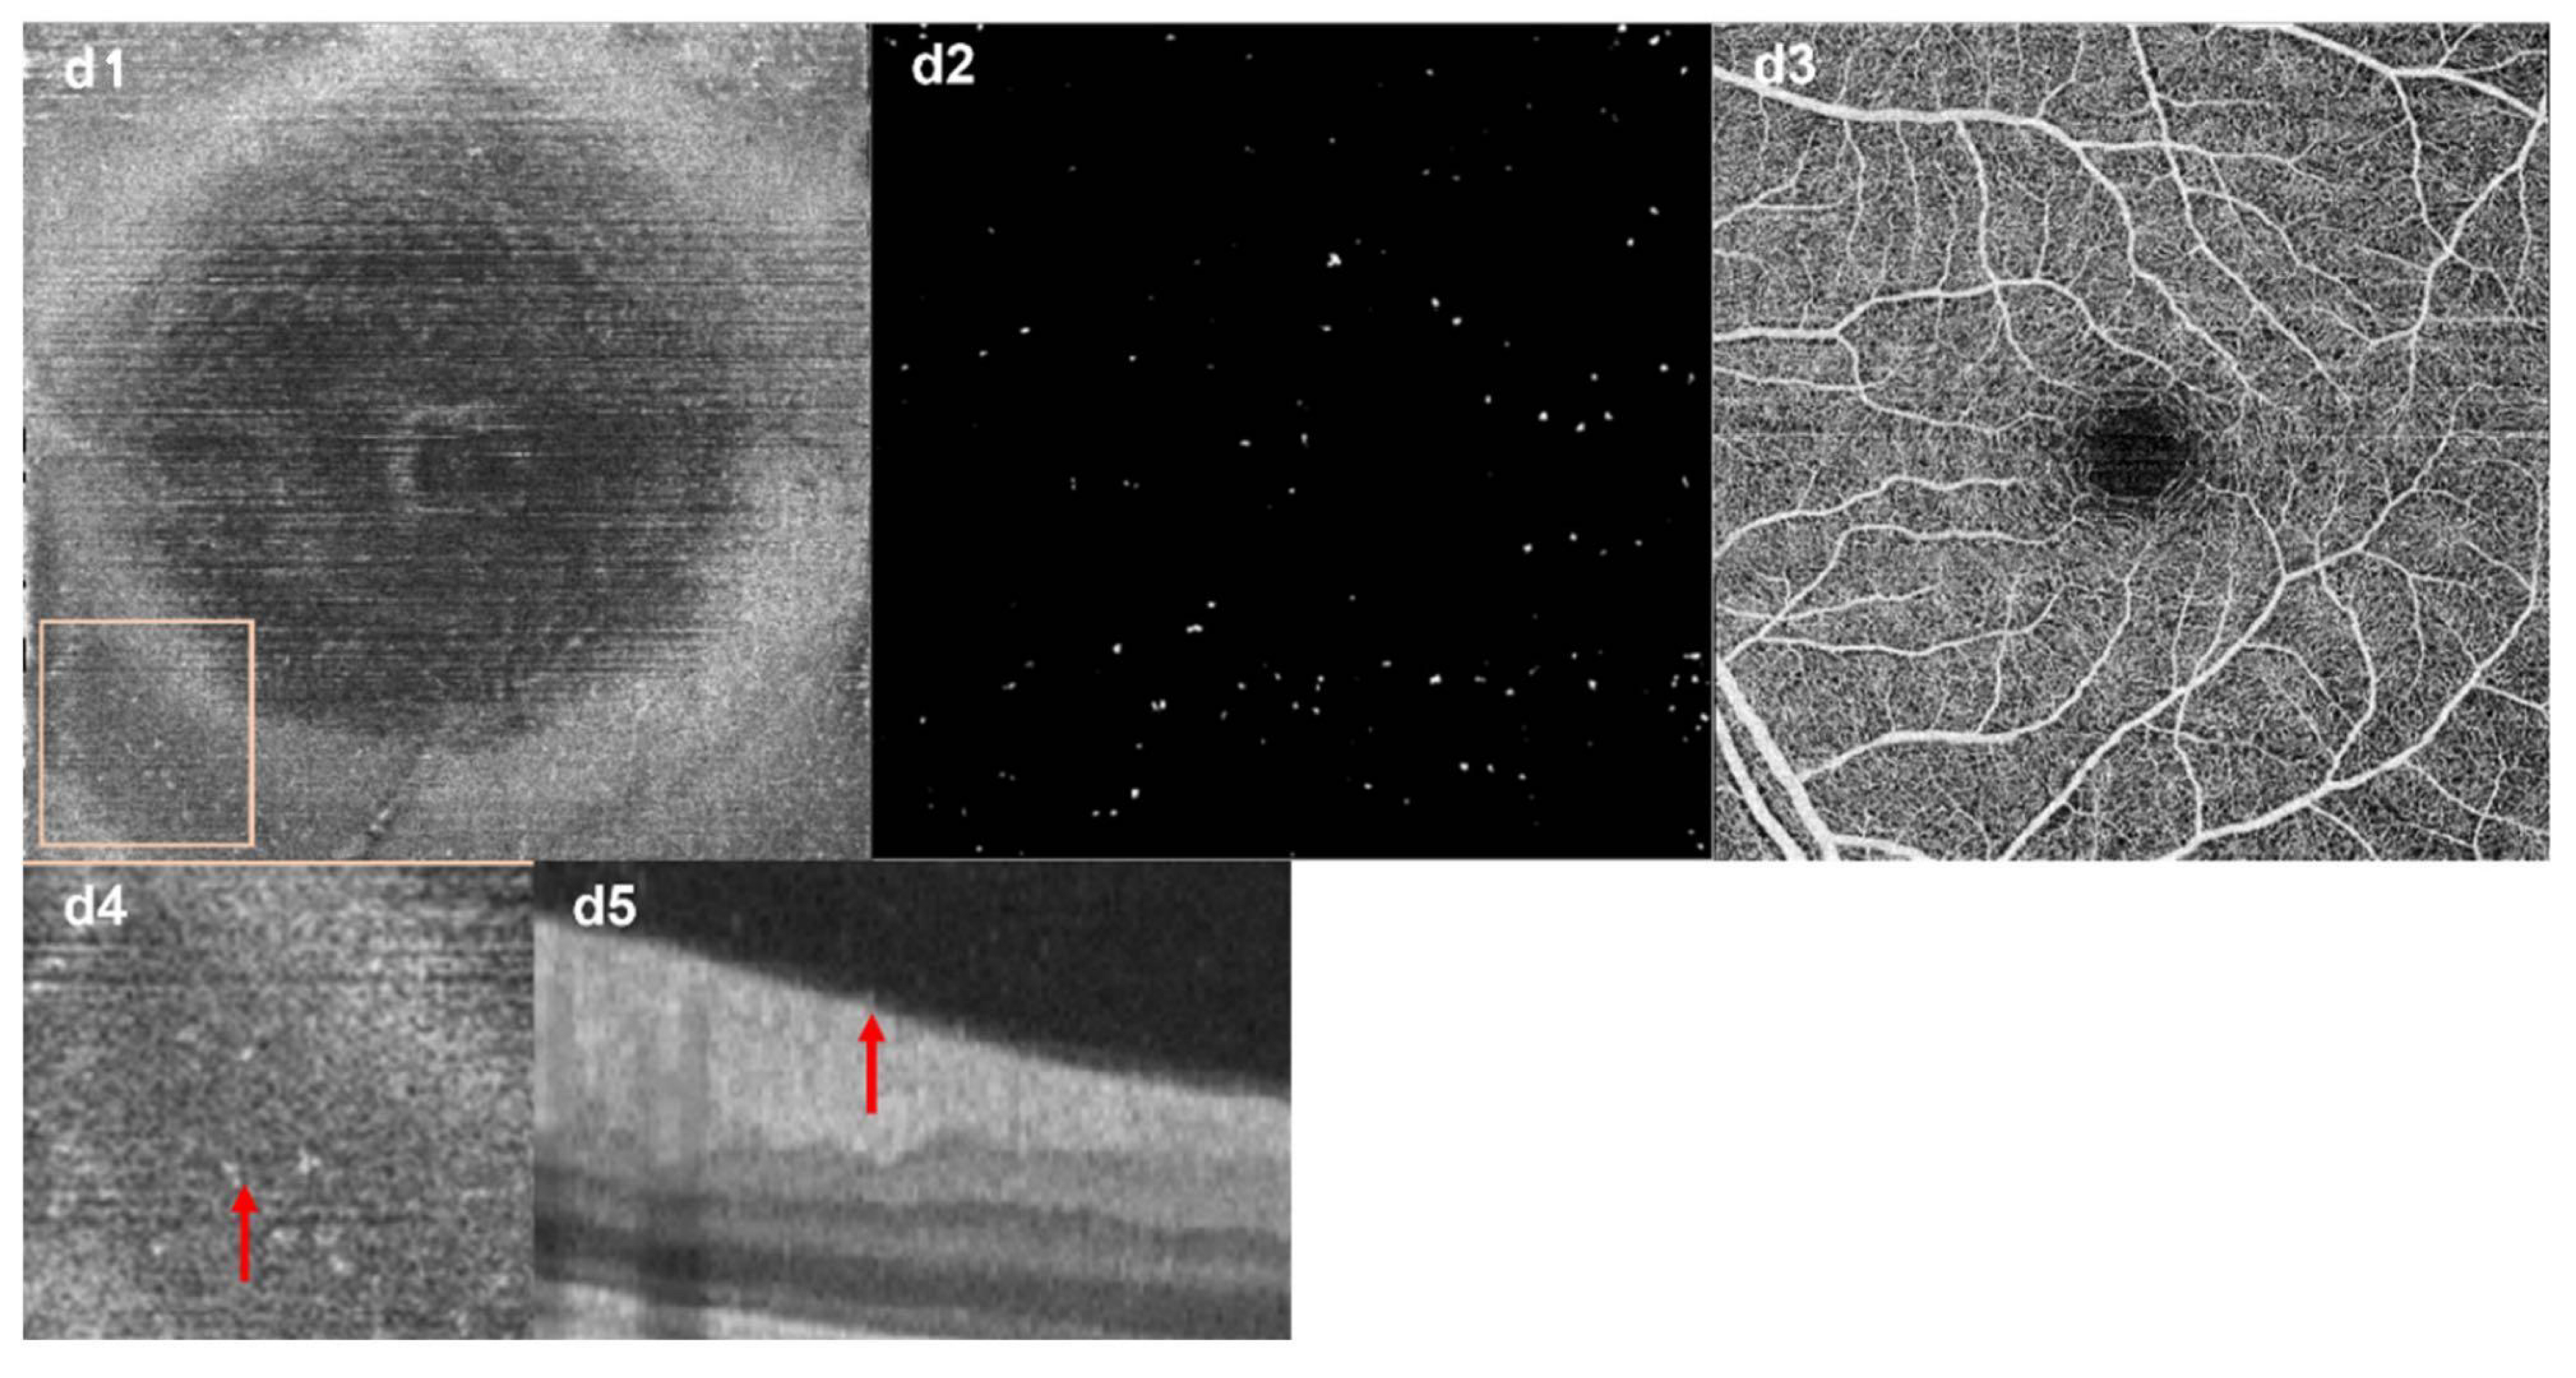

- Castanos, M.V.; Zhou, D.B.; Linderman, R.E.; Allison, R.; Milman, T.; Carroll, J.; Migacz, J.; Rosen, R.B.; Chui, T.Y. Imaging of Macrophage-Like Cells in Living Human Retina Using Clinical OCT. Investig. Opthalmol. Vis. Sci. 2020, 61, 48. [Google Scholar] [CrossRef] [PubMed]

- Ong, J.X.; Nesper, P.L.; Fawzi, A.A.; Wang, J.M.; Lavine, J.A. Macrophage-Like Cell Density Is Increased in Proliferative Diabetic Retinopathy Characterized by Optical Coherence Tomography Angiography. Investig. Opthalmol. Vis. Sci. 2021, 62, 2. [Google Scholar] [CrossRef]